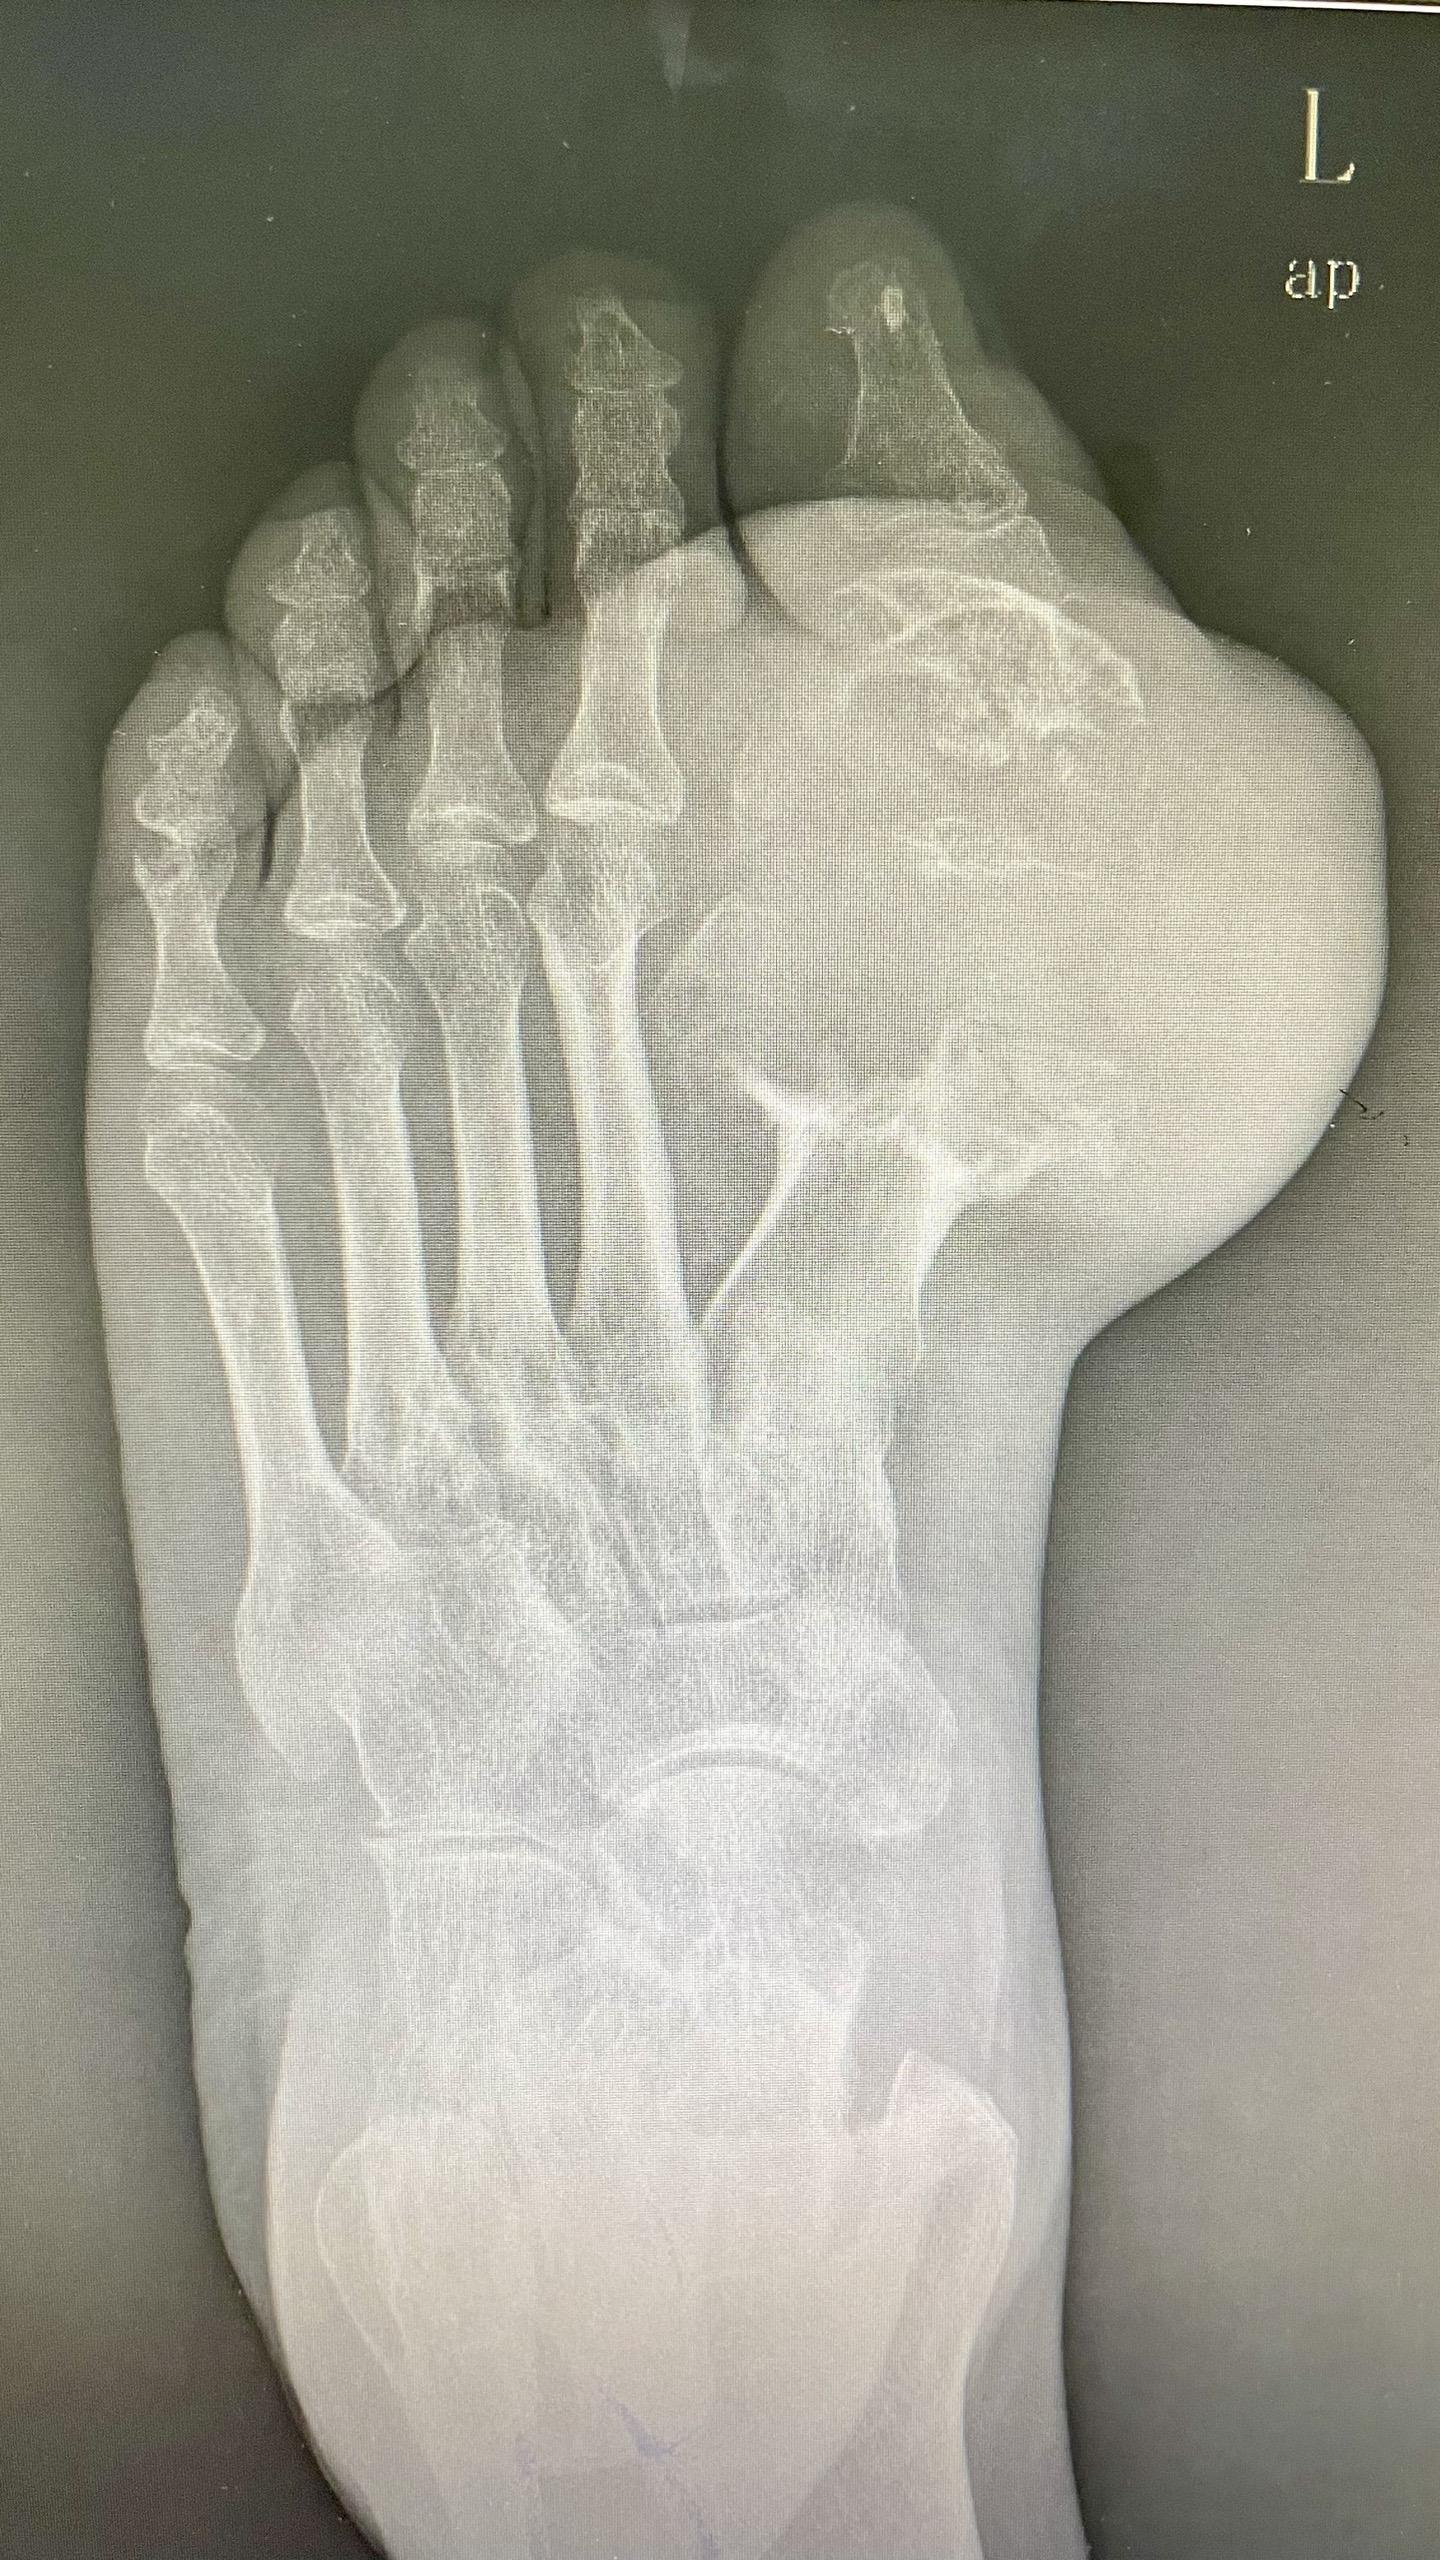

痛风石

痛风石。痛风石竟然会“啃掉”脚骨头 痛风痛风石 痛风患者 痛风之天花板 医生日常